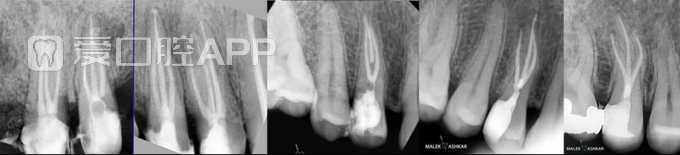

有3根管、4根管的前磨牙的根充 by Dr malek ashkar